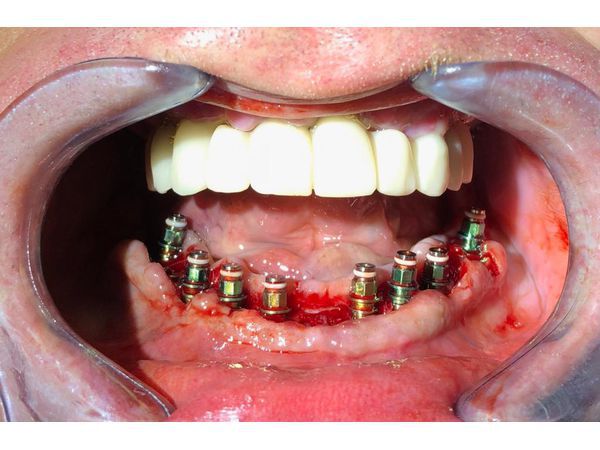

7. Установка имплантатов Osstem на нижнюю челюсть в области резца, клыка, премоляра и моляра слева и справа. Сила введения имплантатов — 50 н/см. Установка формирователей дёсен, рентген контроль. Рана ушита викрилом.

8. Через двое суток установка трансферов на имплантаты нижней челюсти, снятие слепка с целью изготовления абатментов с винтовой фиксацией для формирования эстетического контура прорезывания.

9. Припасовка абатментов нижней челюсти. Припасовка и коррекция хирургического шаблона на нижней челюсти. Закрытие шахт коронок клипом.